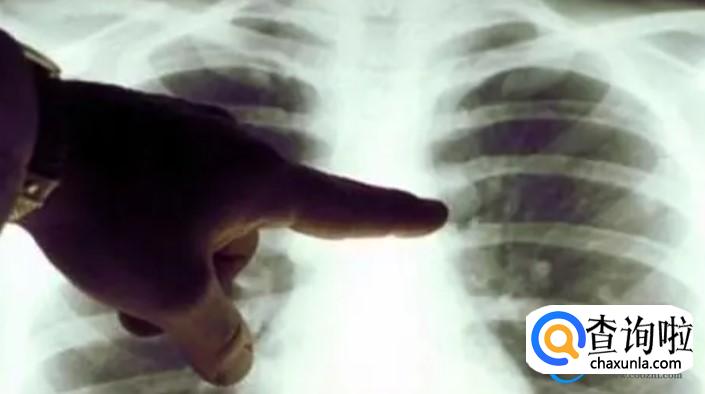

白肺其实是肺炎当中比较严重的一种症状,通过CT检查时发现肺部双侧病变已经达到了75%以上。针对新冠白肺大家也不需要过分的担心,目前医生对于白肺会有明确的治疗方法。